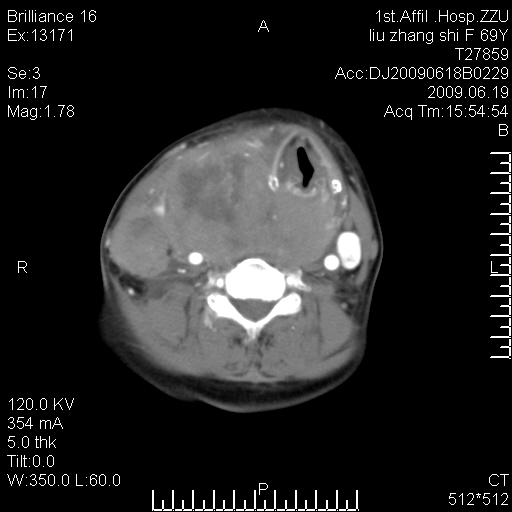

标题: CT26782:女,69岁,颈部占位,3天后公布病理结果。

【病理证实系列】女,69岁,颈部占位,有病理结果,3天后公布。(由于病例时间较久,临床资料不全,请网友见谅)本系列将有几百种常见、少见及罕见病例,均经病理证实。病例资料来自郑州大学第一附属医院。与网友共享,本人有空就发。

甲状腺癌并颈部淋巴结转移。感谢楼主的良苦用心,谢谢。

甲状腺癌并颈部淋巴结转移。

需与鼻咽癌鉴别!

支持甲状腺癌广泛侵及周围结构并颈部淋巴结转移。

鉴别:淋巴瘤、恶性神经源性病变、恶性纤维组织细胞瘤。

病理结果:颈部非霍奇金淋巴瘤。